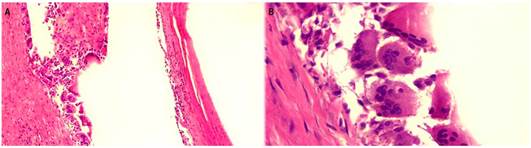

La pieza quirúrgica se envió al servicio de patología, en el que se reconoció un segmento colónico de 15 cm con diámetros variables de 2 a 4 cm, seroso de color pardo claro cubierto en toda su extensión por un mesenterio que medía hasta 4 cm. La mucosa se había remplazado en más del 80 % por formaciones quísticas de aire, la mayor de ellas medía 4,5 x 4 cm y la menor, 2 x 1 cm; con una pared que medía 0,1 cm; estas lesiones también se pudieron observar de menor tamaño en el mesenterio circundante (Figura 2). Además, en el análisis microscópico se encontró en la submucosa y la capa muscular propia múltiples lesiones quísticas (Figura 3), asociadas con células gigantes multinucleadas tipo cuerpo extraño y macrófagos (Figura 4). Las lesiones se extendieron hasta la subserosa, donde también se observaron células mesoteliales reactivas. Con estos hallazgos se confirmó el diagnóstico de neumatosis quística intestinal.

Figura 4 Histológicamente, se evidencian estructuras quísticas revestidas por células gigantes multinucleadas tipo cuerpo extraño e infiltrado inflamatorio mononuclear. A. 4 X. B. 40 X.

La neumatosis quística intestinal es una patología infrecuente caracterizada por estructuras quísticas en la submucosa intestinal, subserosa y muscular propia en cualquier parte del tracto gastrointestinal, con mayor frecuencia en el colon 3. Se considera que más del 80 % de los casos de neumatosis quística intestinal son iatrogénicos; sin embargo, se atribuye en otras ocasiones a un origen bacteriano, metabólico o pulmonar, trastornos del tejido colágeno, síndrome de inmunodeficiencia humana o consumo de algunos fármacos específicos como glucocorticoides 1,6, lo que provoca el aumento de la presión intraluminal y fuerza la salida de gas a través de la mucosa alterada; esto produce una respuesta tisular, la cual se puede evidenciar por la presencia de células gigantes multinucleadas asociadas con macrófagos a nivel histológico 3, cuyas complicaciones pueden requerir manejo quirúrgico 7.

Macroscópicamente, la neumatosis intestinal se caracteriza por múltiples estructuras similares a quistes en la mucosa de la pared intestinal, en algunas ocasiones se describe con aspecto cerebriforme. Microscópicamente, se reconocen estructuras similares a quistes de tamaño variable sobre la mucosa, submucosa o muscular propia con tamaños desde milímetros hasta algunos centímetros; como características histológicas, estas estructuras están revestidas por macrófagos, células gigantes multinucleadas tipo cuerpo extraño e infiltrado inflamatorio mononuclear 3. Los quistes tempranos pueden estar revestidos por células endoteliales, por lo que se puede interpretar en algunas ocasiones como distensión de los vasos linfáticos 11.

El contenido de los quistes es una mezcla de nitrógeno e hidrógeno con cantidades variables de oxígeno, dióxido de carbono, butano, propano, metano, etano y argón, que generan una respuesta inflamatoria de tipo cuerpo extraño mediada por células gigantes multinucleadas que expresan cúmulo de diferenciación 68 (CD68) en los estudios complementarios de inmunohistoquímica 11.